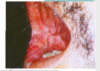

Paracoccidioidomicose

lesao mucosa oral-> RS

estomatite moriforme (toda lesão na boca é chamada de estomatite); moriforme é porque tem aspecto mamilonado, ou seja, lembra uma amora